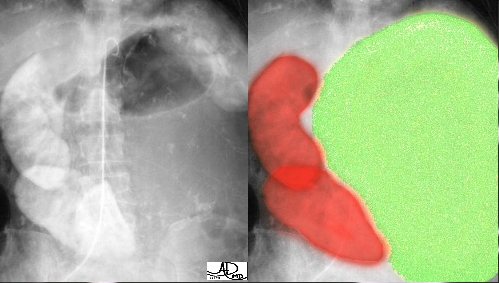

This massive adrenal carcinoma (in green overlay) occupies almost the entire left side of the abdomen, and is so bulky that it has literally pushed the left kidney (red overlay) down to the pelvis, and rightward toward the right kidney. Sometimes adrenal carcinomas can produce hormones which can have functional effects, characterised by the type of hormone that is produced in excess. Courtesy of: Ashley Davidoff, M.D. |

This image represents a solid mass that is half the size of the kidney below the mass. A mass of this size typically indicates a primary carcinoma, however, this case represents a large pheochromocytoma. Courtesy of: Ashley Davidoff, M.D. |